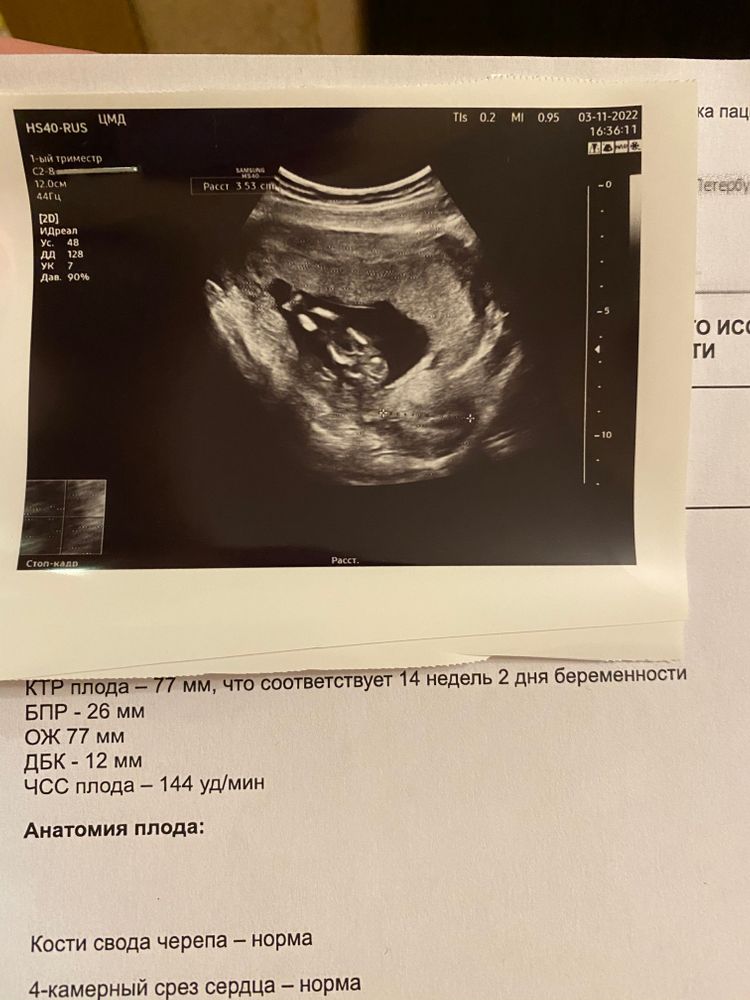

Девушки, 20.10 ходила на первый скрининг в ЖК, там обнаружили ретрохориалтную гематому 13х5мм, симптомов и признаков никаких не было, меня тогда это ещё насторожило, гинеколог прописала дюфастон до 20 недели и свечи, сказала что должно все выйти коричневыми выделениями. Сегодня был повторный приём у гинеколога , она по узи (20.10) сказала у меня предлежание плаценты, полный половой покой, дальше принимать дюфастон, я ей сказала что никаких выделений у меня не было, она сказала «значит сама рассосалась». Меня это насторожило, решила пройти узи в платной клинике. По результатам, никакой гематомы у меня нет и не было (она смотрела заключение врача узиста 20.10 и снимок), по узи плацента у меня очень даже высоко ( с ее слов идеально, лучше и быть не может) с малышом тоде все замечательно, она мне посоветовала сменить поликлинику и бросить пить дюфастон и вставлять свечи. Что посоветуете, послушать врача гинеколога и дальше лечиться дюфастоном и смериться со своим диагнозом или как сказала врач из платной поликлиники, перестать его принимать и у меня все замечательно?